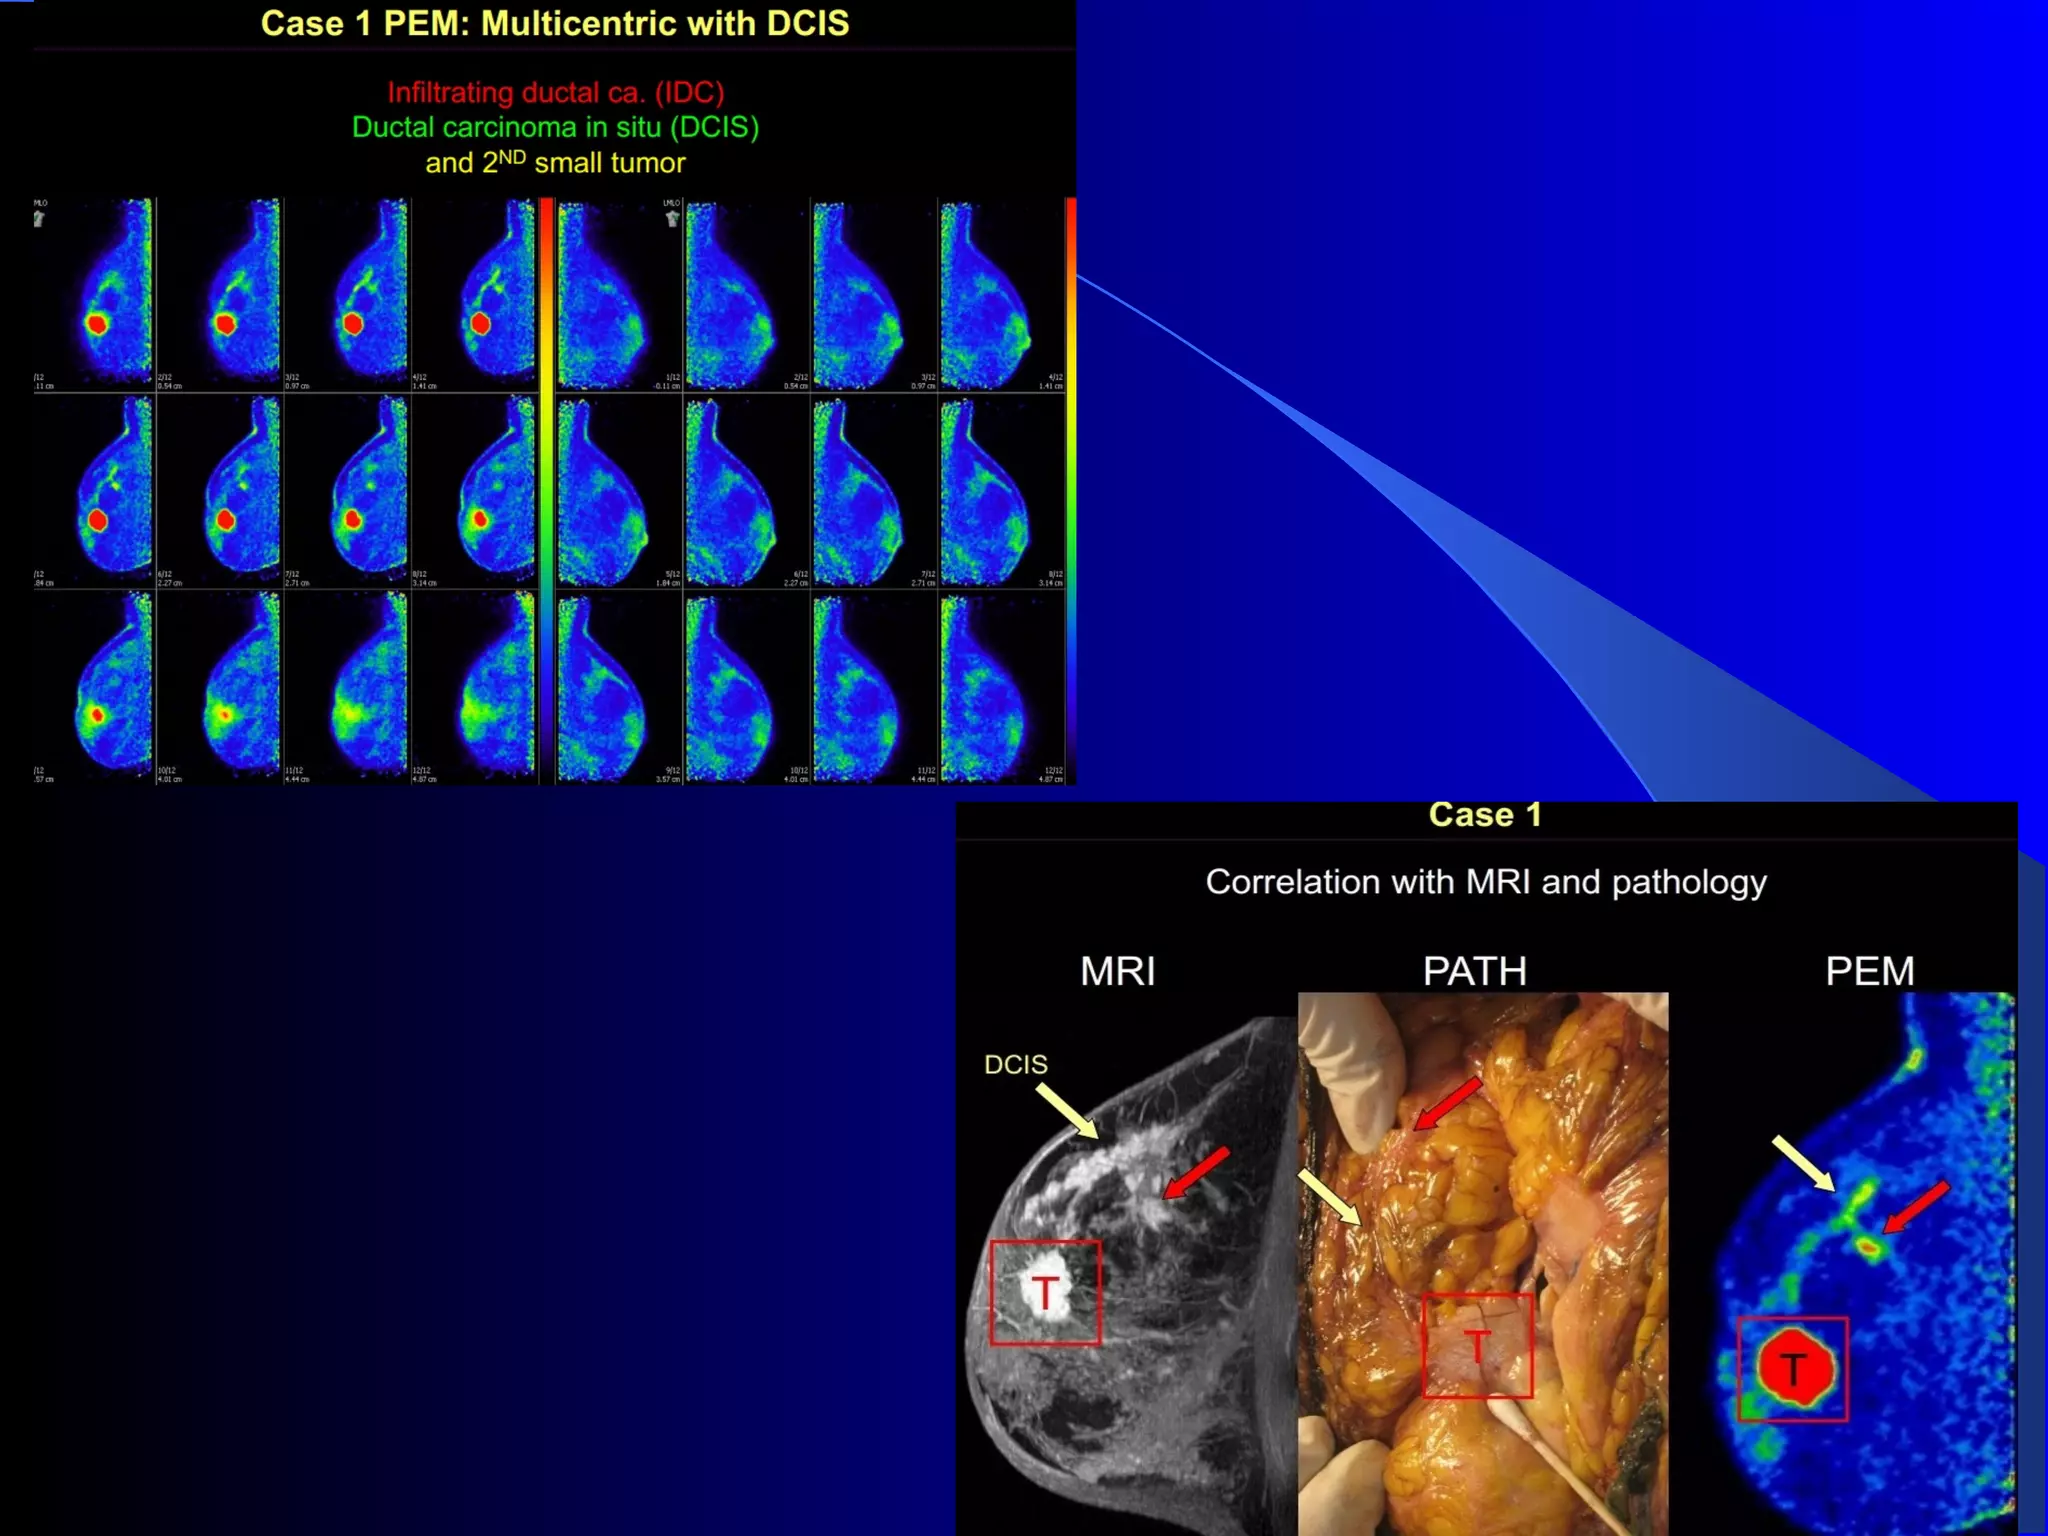

PEMPEM

 Positron Emission Mammography

 PEM is a specialized & improved

form of PET for imaging breasts

and other small body parts.

 Camera and detectors are closer to

the area affected with cancer which

produces a very sharp detailed

image of tumors and cancerous

tissue.

 Can see cancers as small as 1.5 –

2mm about the width of a grain of

rice.

 Also allows for the earlier

detection of elusive cancers such

as DCIS (ductal carcinoma in situ).

Understand the differences between whole-body PET and PEM

Spatial Resolution

better spatial resolution (1-2 mm vs. 5-10 mm). This comes at the

cost of field-of-view